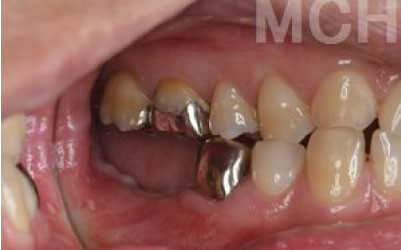

2 歯が傾いてくる、落ちてくる

歯はお互いに支え合ってバランスを取っています。ですので、歯が抜けるとその支えがなくなり、抜けた部分の隣の歯が倒れたり、上の歯が下に下がってくることがあります。